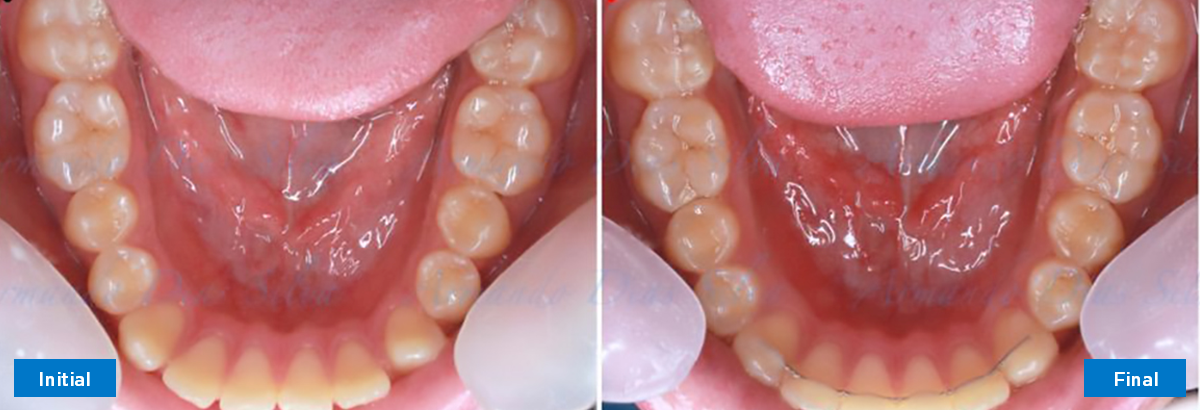

• Espaciamiento leve de las arcadas superior e inferior (deficiencia transversal de 3,45 mm)

• Incisivos superiores e inferiores proclinados

• Retroclinar los incisivos inferiores

N.º de alineadores -Superior: 24 Inferior: 16

• Incisivos inferiores retroinclinados, que mejoran la estabilidad a largo plazo

Retención: Arco superior retenido con retenedor transparente. Arco inferior retenido con retenedor lingual unido de canino a canino.